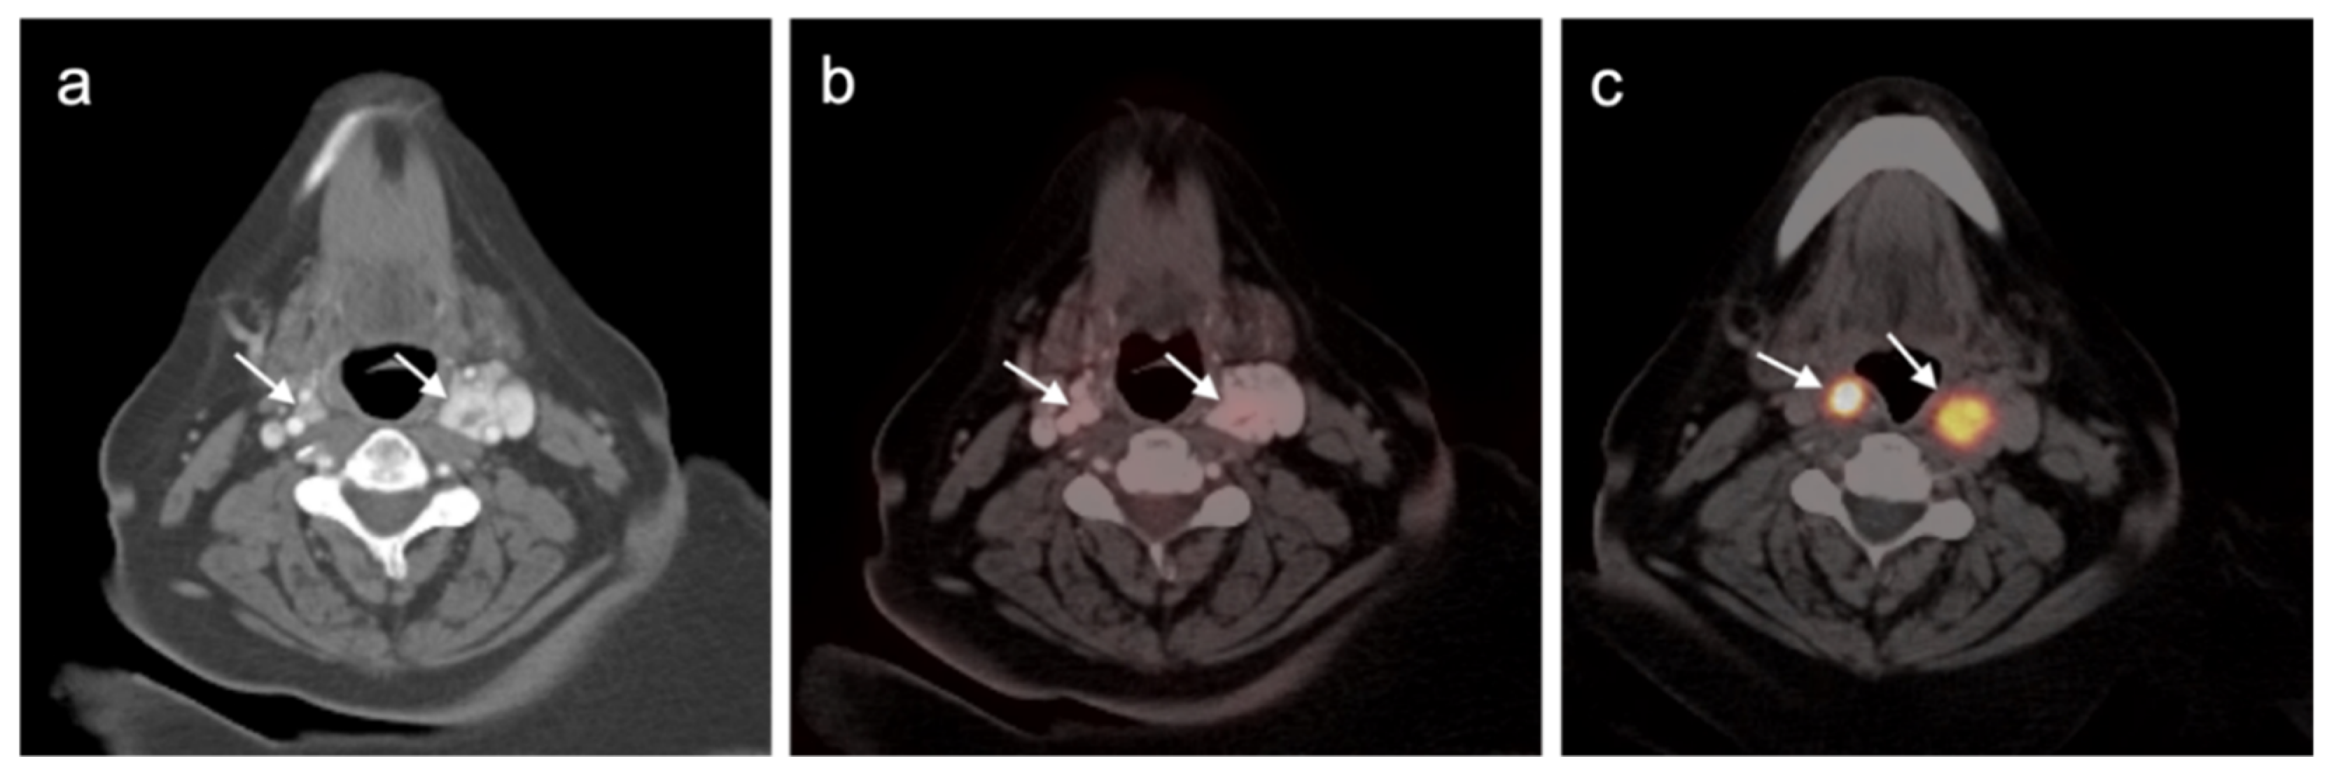

4.5. Pheochromocytoma and Paraganglioma